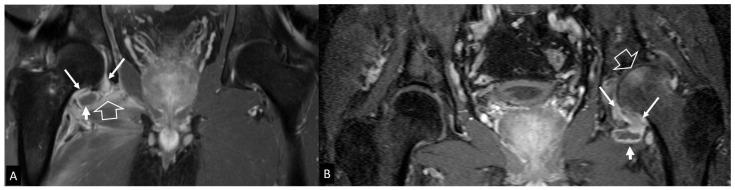

A series of conditions can mimic musculoskeletal infections on imaging, complicating their diagnosis and affecting the treatment. Depending on the anatomical location, different conditions can manifest with clinical and imaging findings that mimic infections. Herein we present a wide spectrum of the musculoskeletal disorders of the axial skeleton, long bones, peripheral joints, and soft tissue that may manifest as infectious processes, and we focus on the potential mimics of osteomyelitis, septic arthritis, and infectious spondylodiscitis that are common in clinical practice. We present the typical imaging characteristics of each musculoskeletal infection, followed by mimicking conditions.

一系列病症在影像学上可模拟肌肉骨骼感染,使诊断复杂化并影响治疗。根据解剖位置的不同,不同病症可表现出类似感染的临床和影像学表现。在此,我们展示了轴向骨骼、长骨、外周关节和软组织的广泛肌肉骨骼疾病,这些疾病可能表现为感染过程,并且我们重点关注临床实践中常见的骨髓炎、化脓性关节炎和感染性脊椎间盘炎的潜在模仿病症。我们介绍了每种肌肉骨骼感染的典型影像学特征,随后是模仿病症。